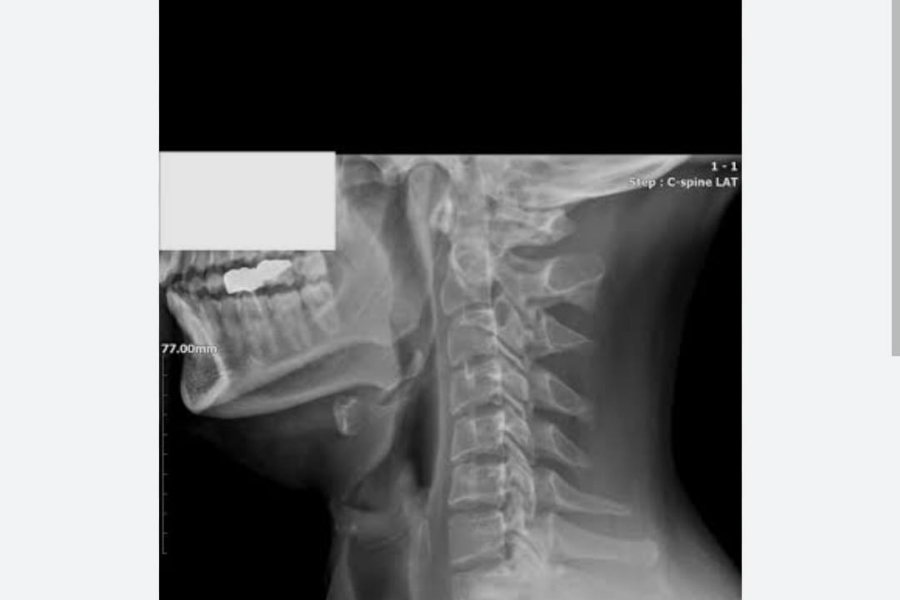

Boyun Düzleşmesi Nedir?  Tedavisi ve Belirtileri Nelerdir?